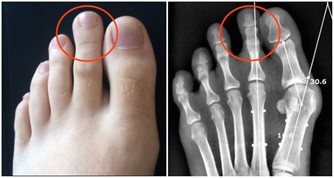

香菜中含有維生素B1,缺乏維生素B1會引多種神經炎症,如腳氣病。